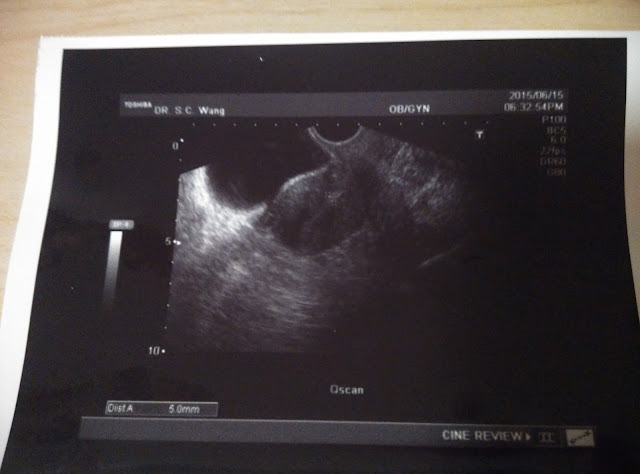

6月17日,星期三。

今天要去黃醫生那裡覆診,看看卵泡及內膜的生長情況。

還好醫生檢查後,卵子還在。

她說已大了一點點,約有1.7cm,

但我問她看照片上只有1.65cm,不是比之前還細了嗎。

她解釋因角度的問題,剛剛看到有其他角度是大一點的。

至於內膜就厚了一點點,由5mm增厚至6mm。

雖然是厚了,但依然未夠。

不過估不到的是她要我打破卵針了,我帶著一點疑問,

明明內膜還沒好,現在打會有用嗎?

她表示我還有之前開的藥要吃,而且那個破卵針也會令內膜增厚,

所以沒有問題。

她說36小時後做功課。

再者,她多開了一枝針給我,要我後日再打。